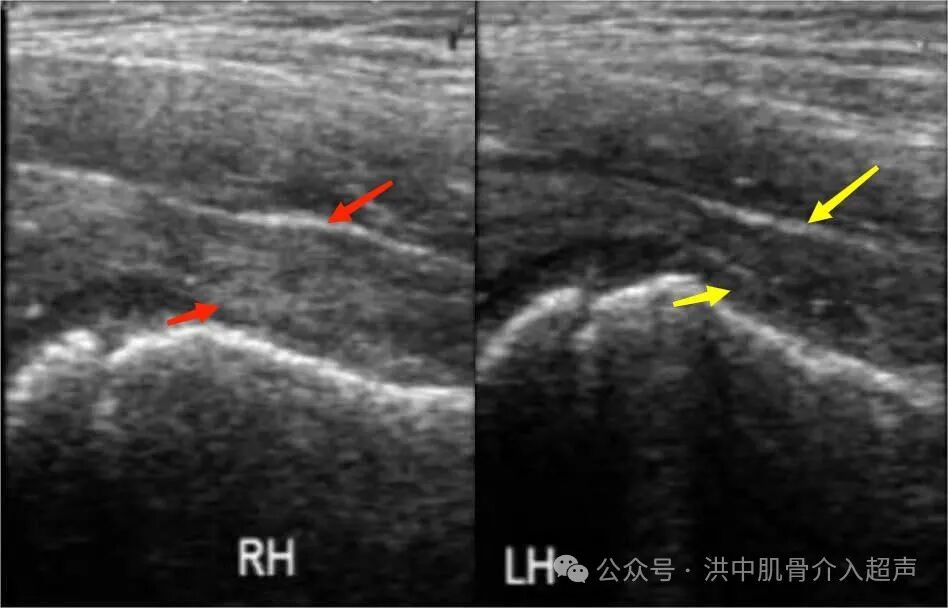

彩超诊断髋关节滑膜炎可分为关节囊肿胀型和关节腔积液型。

关节腔积液型:患侧股骨颈颈前间隙较健侧明显增宽大于1mm(儿童2mm有病理意义),关节腔前隐窝内有积液(红色箭头),伴或不伴滑膜增厚。